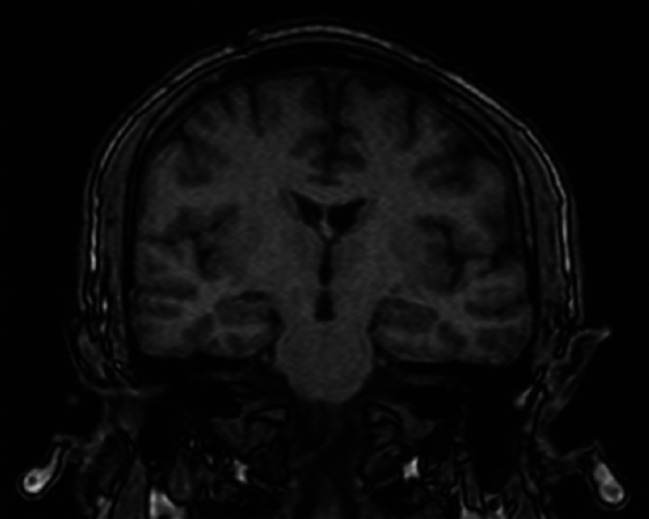

Clinical presentation: We present the clinical report of a 42-year-old male who, after a car accident, exhibited core symptoms of PTSD along with symptoms of self-organization disorders. While these symptoms persisted, the patient developed dissociative amnesia years after the trauma. Neuroimaging studies, psychometric tests, reviewed hospital records, and clinical interviews were conducted to speculate on the differential diagnosis of organic psychiatric conditions and potential diagnoses. The possible relationship between dissociative amnesia and complex post-traumatic stress disorder was examined.